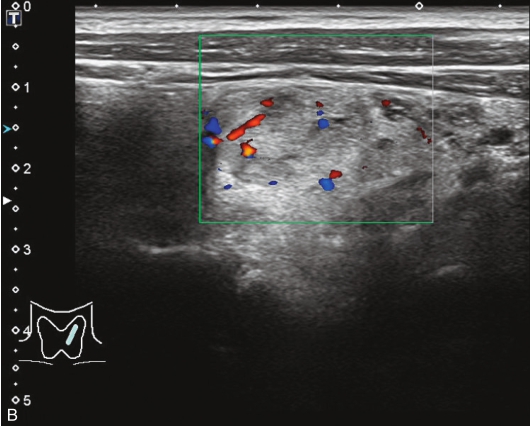

甲状腺囊肿常规超声表现为边界清晰、形态较规则的无回声结节,内可见点状强回声,后伴“彗星尾”征,CDFI内部无明显血流信号,见图1-3-1。

图1-3-1 甲状腺囊肿常规超声声像图

A.甲状腺左叶纵切面;B.CDFI血流图